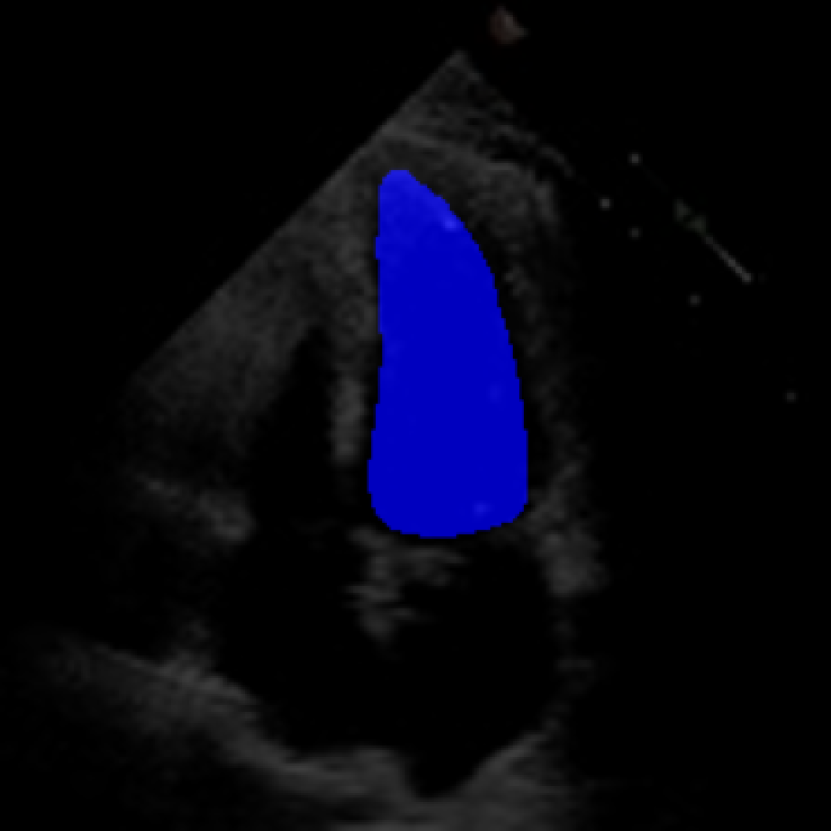

The model for LVD measurement was built using a modified version of the DeepLabV3+ architecture [35], with an EfficientNetV2S [36] backbone replacing the original ResNet50 [37]. This change was necessitated by the higher resolution of the EchoNet-LVH videos, which typically have dimensions of either (1024,768) or (800,600), compared to the (112,112) resolution of the Echonet-Dynamic dataset.

The ConFormer model achieved a mean absolute error (MAE) of approximately 6 for the combined measurements of the IVS, LVID, and LVPW. This performance is notable when compared to the EchoNet-LVH model, which achieved MAEs of 1.7mm for IVS, 3.8mm for LVID, and 1.8mm for LVPW when fine-tuned on the Cedars-Sinai Medical Center (CSMC) dataset.

Despite its significantly reduced parameter count, the ConFormer model demonstrates robust performance across different video resolutions and frame rates. These results suggest that the ConFormer model could be a valuable tool for automating the measurement of ventricular wall thickness in echocardiogram videos, potentially leading to more accurate and efficient diagnoses of left ventricular hypertrophy.